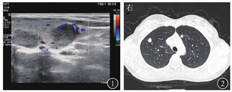

患者女,38岁,因"体格检查发现双肺多发占位3 d"于2019年10月21日入院。患者无咳嗽、咳痰、发热、盗汗等症状,体格检查示:甲状腺无肿大、压痛;全身浅表淋巴结未触及;呼吸运动正常,双肺呼吸音清,无干湿性啰音。入院后完善相关检查。超声检查示:甲状腺双侧叶实性结节[甲状腺影像报告和数据系统(throid imaging reporting and data system,TIRADS)分级为4a级,建议行超声引导下细针吸取(fine-needle aspiration)],甲状腺右侧叶囊实性结节(TIRADS分级为3级),见图1。胸部CT检查示:甲状腺双叶低密度结节,双肺多发结节,见图2。PET-CT检查示:双肺多发结节代谢较活跃,甲状腺双叶多发低密度结节代谢活跃。T-SPOT.TB示抗原A[早期分泌抗原靶-6(early secretory antigenic target-6,ESAT-6)]孔斑点数为56个,抗原B[培养滤液蛋白10(culture filtrate protein 10,CFP-10)]孔斑点数为50个;抗酸染色未见抗酸杆菌;血清三碘甲腺原氨酸(triiodothyronine,T3)、甲状腺素(thyroxine,T4)、游离三碘甲腺原氨酸(free triiodothyronine,FT3)、游离甲状腺素(free thyroxine, FT4)、促甲状腺激素(thyroid-stimulating hormone,TSH)均正常,结核特异性分泌抗原抗体、结核分枝杆菌抗体IgM及IgG均为阴性。行超声引导下甲状腺结节穿刺细针吸取细胞学检查(图3),在多普勒超声引导下以22 G穿刺针进入结节,反复提拉,快速对结节抽吸约10~15次,并旋转针尖,取病灶的不同部位,抽出物以液基固定送病理检查。采用无菌棉球覆盖穿刺部位,按压5~10 min以防出血。病理检查显示:甲状腺右叶下极肉芽肿性炎伴坏死,结核不除外,见图4;甲状腺左叶下极考虑结节性甲状腺肿;肺穿刺活组织病理检查示肉芽肿性炎伴坏死,倾向结核,见图5。结合临床病史,以及实验室、影像学检查,基本可以诊断为肺结核合并甲状腺结核。